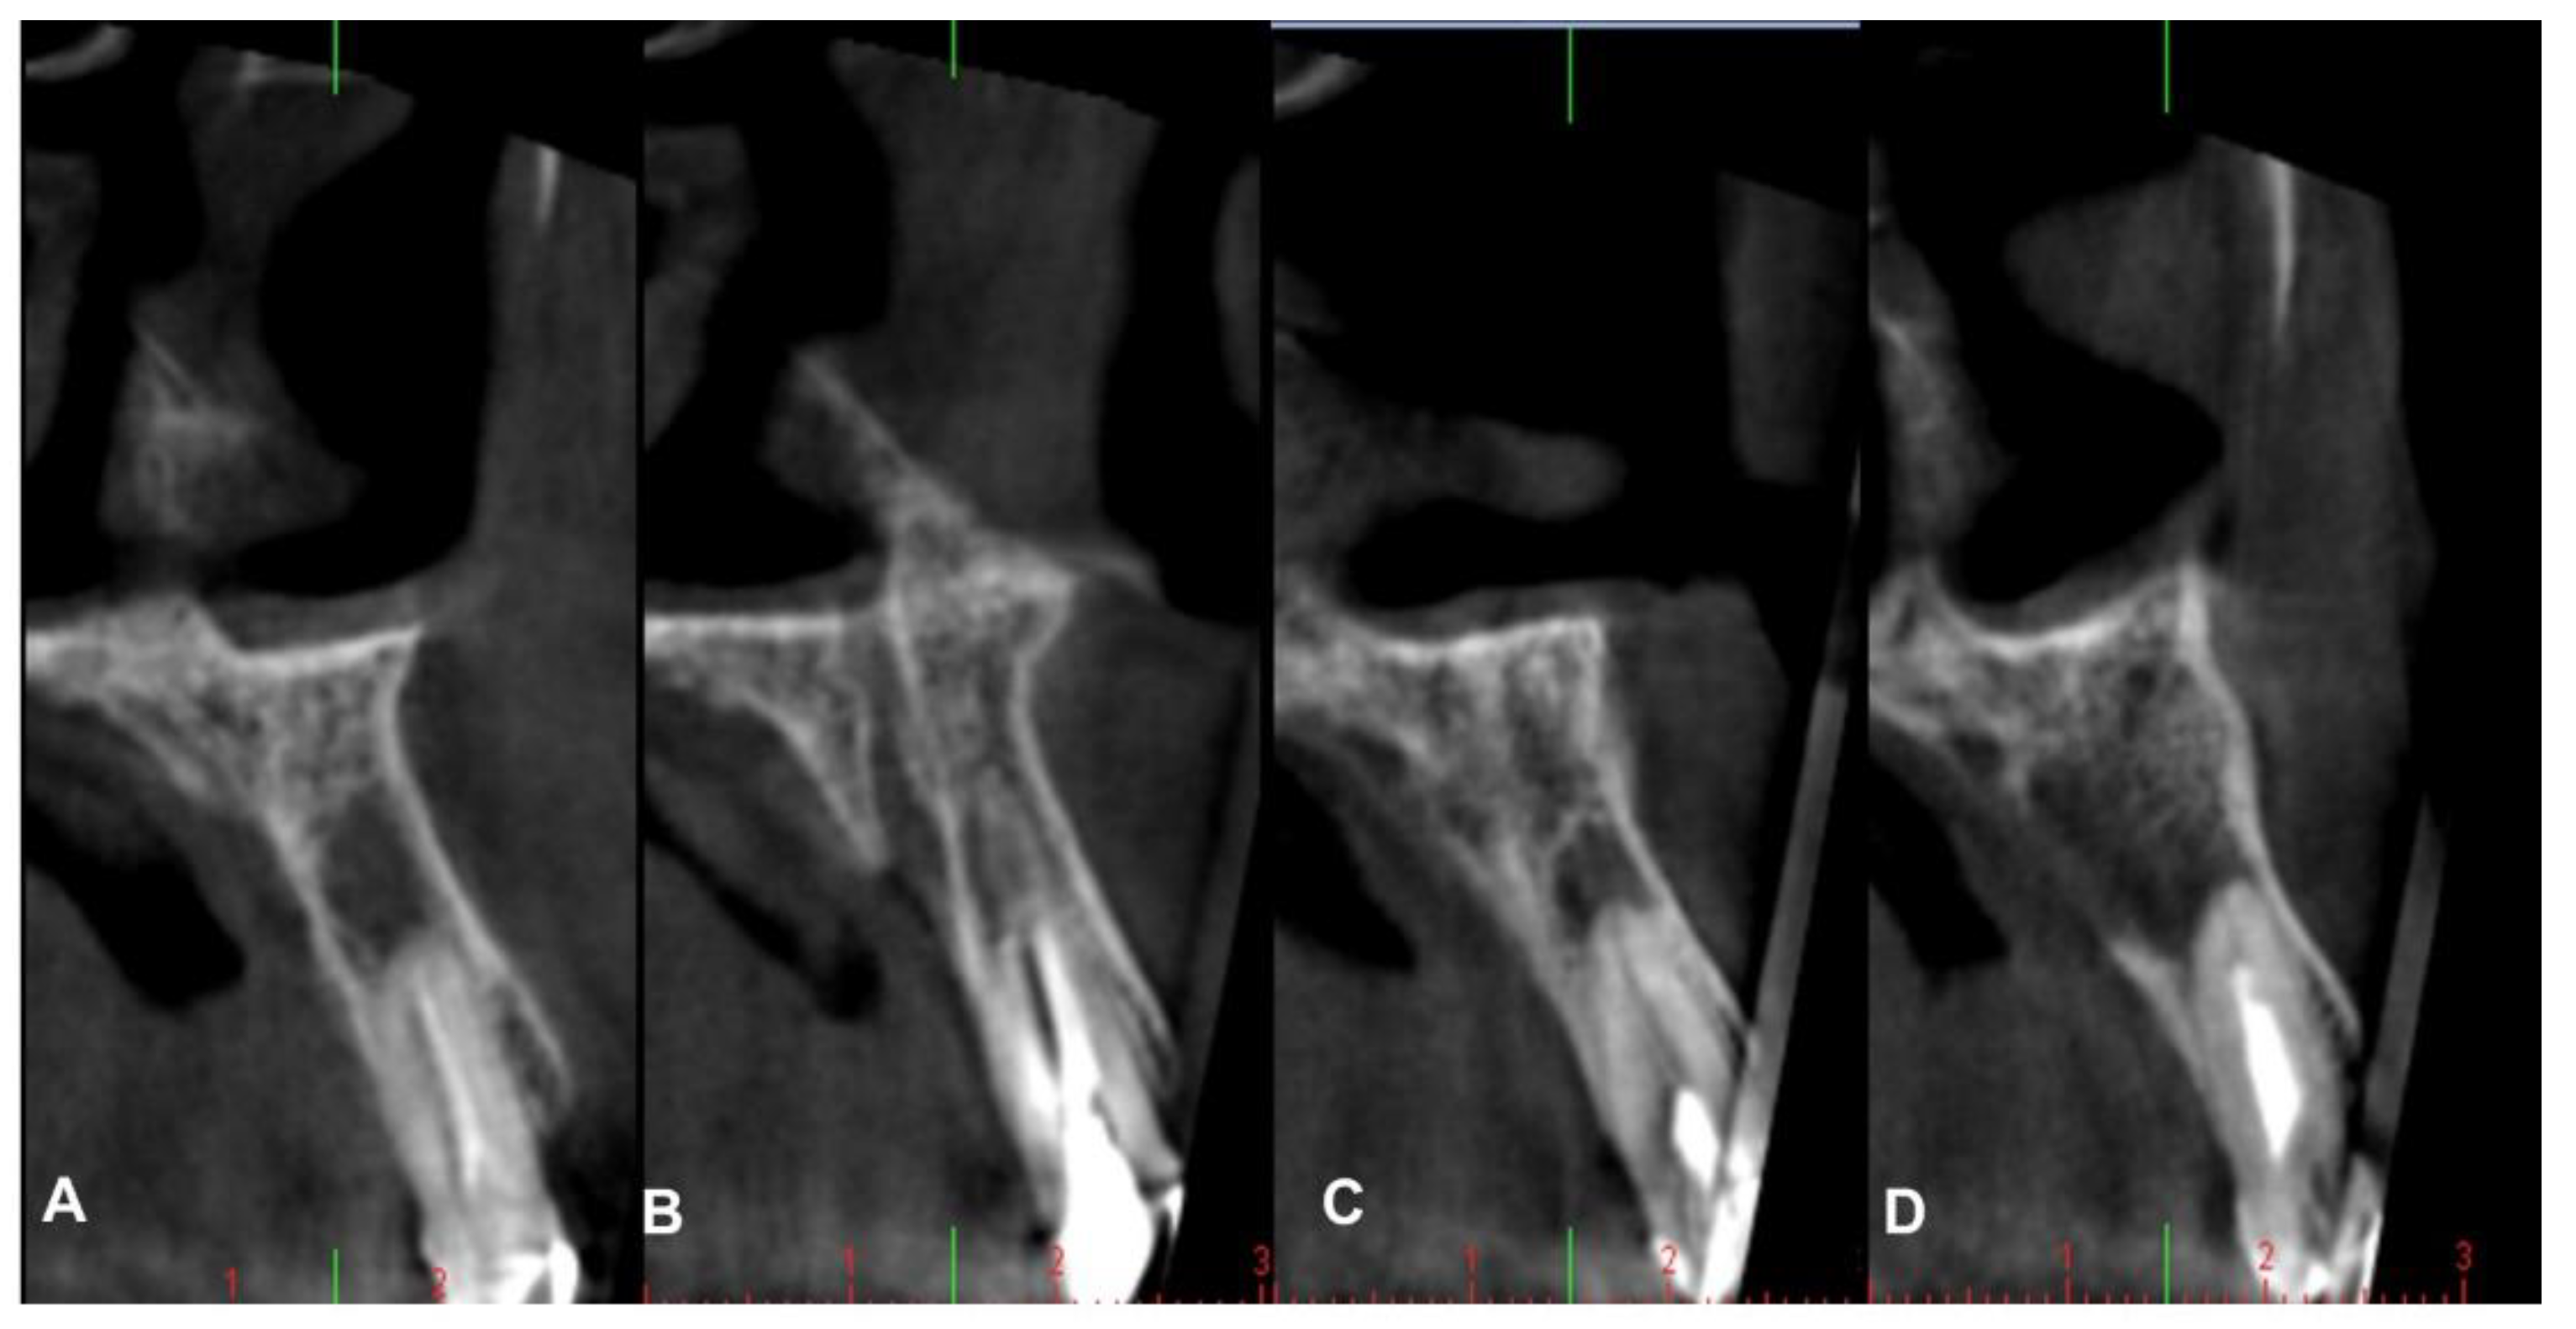

4.2. Patient No. 2

4.3. Patient No. 3

4.4. Patient No.4

4.5. Patient No.5